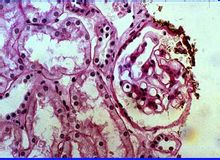

(1) 光鏡檢查:呈瀰漫性系膜細胞增生伴基質增多。早期以系膜細胞增生為主,晚期系膜基質增多。根據增生程度,可分為輕度、中度、重度三級。系膜內可有少數單核細胞和中性粒細胞浸潤。嚴重者可引起系膜硬化。腎小球毛細血管壁及基底膜正常。腎小管及間質基本正常,隨病變進展,可出現腎小管萎縮、間質炎症細胞浸潤及纖維化。腎內血管一般正常。

(2) 免疫病理:在我國最常見於IgG和C 3沿系膜區或毛細血管壁團塊狀或顆粒狀沉積。也可見於以 IgM沉積為主,有學者將其命名為“IgM腎病”。

(3) 電鏡檢查:呈系膜細胞和/或系膜基質增生,伴電子緻密物沉積。